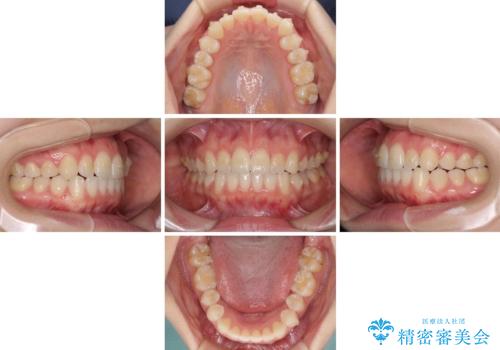

前歯のクロスバイトをインビザライン矯正で改善

- 前歯のデコボコと上下のクロスバイトを気にして来院された患者様です。

インビザラインを用い、IPR(歯と歯の間を削る)と歯列全体を拡大させることで、歯並びを整えていくこととしました。